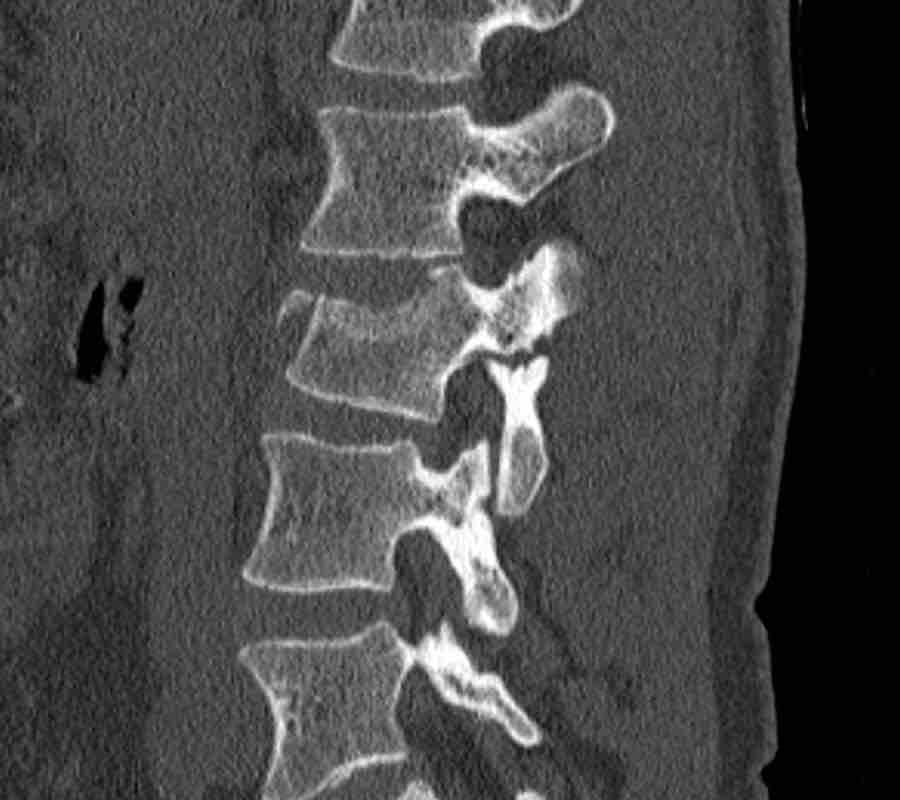

Scroll through the images.

What is the highest AO-type of injury?

Any additional findings?

Then continue with the next images…

Findings

- Black arrows: horizontal fractures through the pedicles as a result of flexion distraction trauma.

- White arrows: soft tissue swelling indicating injury to posterior ligaments.

- Circle: compression fracture of posterior wall (2 points) and two endplates (2 points)

Conclusion

Type B2-A4

Flexion distraction injury with separation on the posterior side and a secondary burst fracture involving both endplates and the posterior wall.